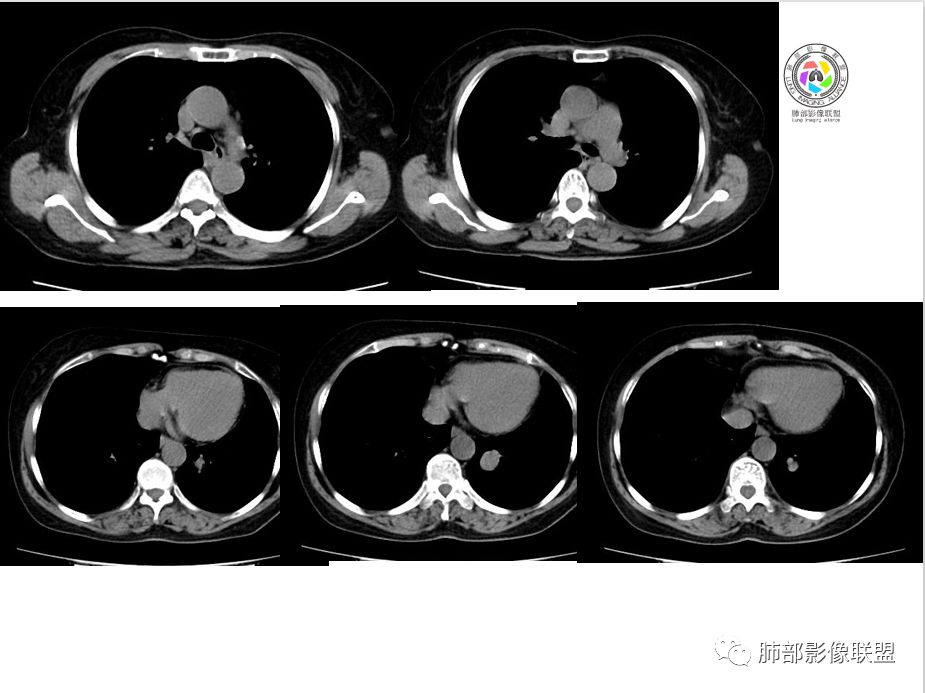

病例资料

Coke with ice:PSP?M-Imaging :良性,PSPShelia:左肺下叶肿块,边缘光整,有血管贴边征,支气管受压推移,延迟强化,考虑PSP?鉴别类癌。不除外恶性

左手:老年女性,无特殊症状,左下肺类圆形结节,边缘清晰,增强见血管贴边,明显强化,无深分叶,无钙化,考虑pspForever:晨读病例病变与血管关系密切 确实psp首先考虑,类癌,腺癌,纤维瘤不能除外没意见:PSP,类癌待排徐超:psp

支气管无关,圆形,光滑,贴别血管稍粗,磨玻璃晕(出血),强化中度,支气管旁疑推挤非阻塞……良性

小木:考虑psp妞妞:支持PSP德芙~云味:考虑psp红日东升:支持PSP崔刚:强化具体CT值忘了标注,轻度强化

目前大家意见一致一米阳光:左肺下叶类圆形病灶,边缘清晰,密度均匀,无分叶毛刺等恶性征像,增强,病变明显强化,血管贴边支持PSP,鉴别类癌,后者弱强化,貌似有分叶南边:

崔刚:当时写报告看好像是支气管确实没堵,受压的改变。

横断位应该显示了这个支气管,当时记得特意考下来图了

M-Imaging :周围有黑边,错构呢?南边:如果明确没堵塞就好办这个最主要的就是这个支气管是否堵塞没堵塞,支持PSP杨泽锋:如果是气管腔内起源的那就要考虑类癌M-Imaging :不见明显冰山征,没有钙化南边:心里不是很踏实,就是没看到支气管全景Forever:强化如果不高 我还是考虑小细胞肺癌或者腺癌

崔刚:有个层面支气管在病灶周边Yiren  Sishui(厶水伊人):其实就是PSP与类癌的鉴别M-Imaging :Forever:如果分不清结构关系了 这个时候强化还是有很大参考价值M-Imaging :周围有黑边崔刚:没有钙化和脂肪,张老师是不是考虑错构瘤?徐超:黑边是想说错构瘤M-Imaging :是啊滴水海:psp也可Forever:不像 觉得ct值有点高。一般错构瘤ct值低于20,没有钙化

滴水海:有黑晕更支持pspM-Imaging :黑边代表局限肺气肿错构瘤,应该和血管没有关系,这例血管贴近毛勤香:考虑PSP或错构瘤,类癌代排南边:我的判断原则:支气管无关——良性、间叶来源良性,强化明显——PSP,尤为明显——糖瘤,不明显——错构瘤